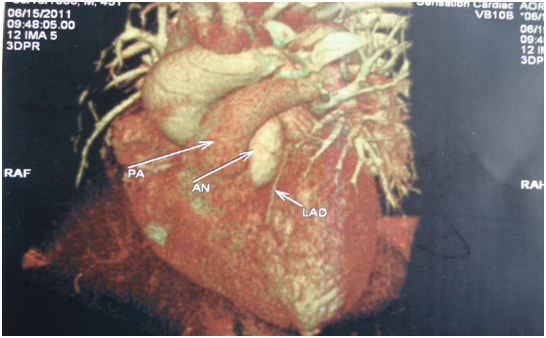

We presenting here a case of the patient with bicuspid aortic valve complicated with aneurysm of right sinus of valsalva. The aneurysm of sinus of valsalva was extracardiac and extending behind the main pulmonary artery and to the left. A 45years old Muslim male patient, carpenter by occupation was admitted with chief complaints of shortness of the breath and chest pain for 1 month. He was having orthopnoea and paroxysmal nocturnal dyspnoea and swelling of the feet. His vitals were stable with pulse rate 96/min, blood pressure 130/50mm Hg, and respiratory rate 14/min. On auscultation S1 was normal and S2 was soft with grade III/VI diastolic murmur in aortic area. Patient was properly investigated. ECG showed sinus rhythm and X-ray chest was showing cardiomegaly. Transthoracic echocardiography showed calcified bicuspid aortic valve, severe aortic regurgitation, grade II mitral regurgitation and that was appeared to be as dissecting flap in ascending aorta with 75% ejection fraction (Figure 1). Computed tomography chest was domne and it showed large pseudo-aneurysm of right sinus of Valsalva (Figures 2 & 3). Computed tomographic angiocardiography was done to define the lesion in the aorta accurately. Computed tomographic angiocardiography (Figures 4 & 5) revealed dysplastic aortic valve, para valvular aneurysmal sac communicating with aortic root as well as to left ventricle (? Pseudo-aneurysm). Routine investigations were done and patient was prepared for surgical intervention. Transoesophageal echocardiography was done in after induction of anaesthesia, which showed a large aneurysmal swelling behind the root of aorta. Conventional sternotomy was done. There were adhesions between pericardium and the heart. All adhesions were lysed. Aortotomy was done after institution of cardiopulmonary bypass. Bicuspid aortic valve and opening of the aneurysm were identified (Figure 6). Distorted, calcified aortic leaflets were excised and the opening of the aneurysm of sinus of valsalva was closed with Dacron patch from inside of the aorta (Figure 7). Aortic valve was replaced with sorin, bileaflet, mechanical valve, size 21 using interrupted ethibond, pladgeted sutures (Figure 8). Postoperative period was uneventful and patient was discharged on 7th postoperative day in good general condition. Patient is doing well in follow up visits.

Figure 4 CT Angiography.

Figure 5 CT Angiography.